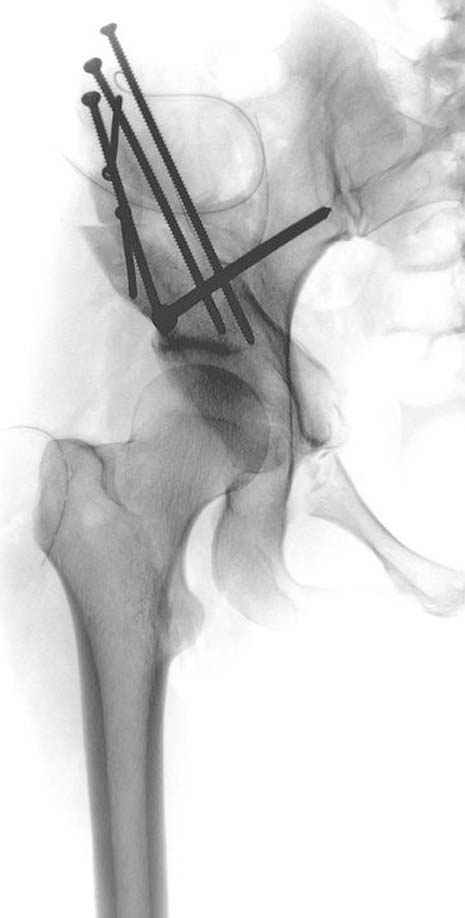

До операции #3

№ 1-3 до операции

Pauwels felt that the problem in certain cases, existed in the bone or cartilage, had lost to withstand pressures of normal magnitude. In many other cases ther existed mechanical abnormalities in the anatomical relationship of the joint leading to a decrease in articular contact surface. These abnormalities: from acetabular side: changes which leads to poor anterior or lateral coverage, steep inclination of soursil, lateralization of center rotation, decrease acetabular depth. From femoral side: shape of femoral head, increasing neck anteversion, neck shaft angle, proximally location of great trochanter. Result of these changes decrease contact area and increase contact stresses and eventually DJD.

Although total hip arthroplasty is a surgical option, it has been associated with a high rate of failure in younger, physically active patients. Both cemented and non-cemented prostheses have shown relatively poor survivor rates in young patients. Patients with DDH are at a high risk for developing early osteoarthritis because the weight supported by the hip joint is concentrated over a smaller surface area when the femoral head subluxates up over the rim of the acetabulum. The goal of treatment is to prevent osteoarthritis in these patients. Redirecting the acetabulum is the most acceptable physiological solution because it optimizes the articular congruency in the joint, increases the containment and coverage of the femoral head, and increases the surface contact area on the weight-bearing surface. The Bernese periacetabular osteotomy (PAO) procedure was developed in 1983 by Reinhold Ganz, MD, Jeffrey Mast, MD, and others in Bern, Switzerland. The procedure was first described in 1988. A Bernese PAO allows the surgeon to move the acetabulum freely in any direction (ie, anteriorly, laterally, medially) as necessary to obtain the best coverage. PAO Advantages: allows correction medially, laterally and anteriorly as needed performed through one incision without violation of the abductors pelvic ring and outlet not disrupted can perform capsulotomy to assess the labrum and check for impingement without compromising acetabular blood supply. Surgical correction of the deficiencies should be aimed at improving the mechanics of the joints so as to lower the intra-articular pressure and allow a reparative response to occur in the articular tissues. Application of the orthopedic surgical principles of planning followed by stable internal fixation are needed to able to offer the functional aftercare.